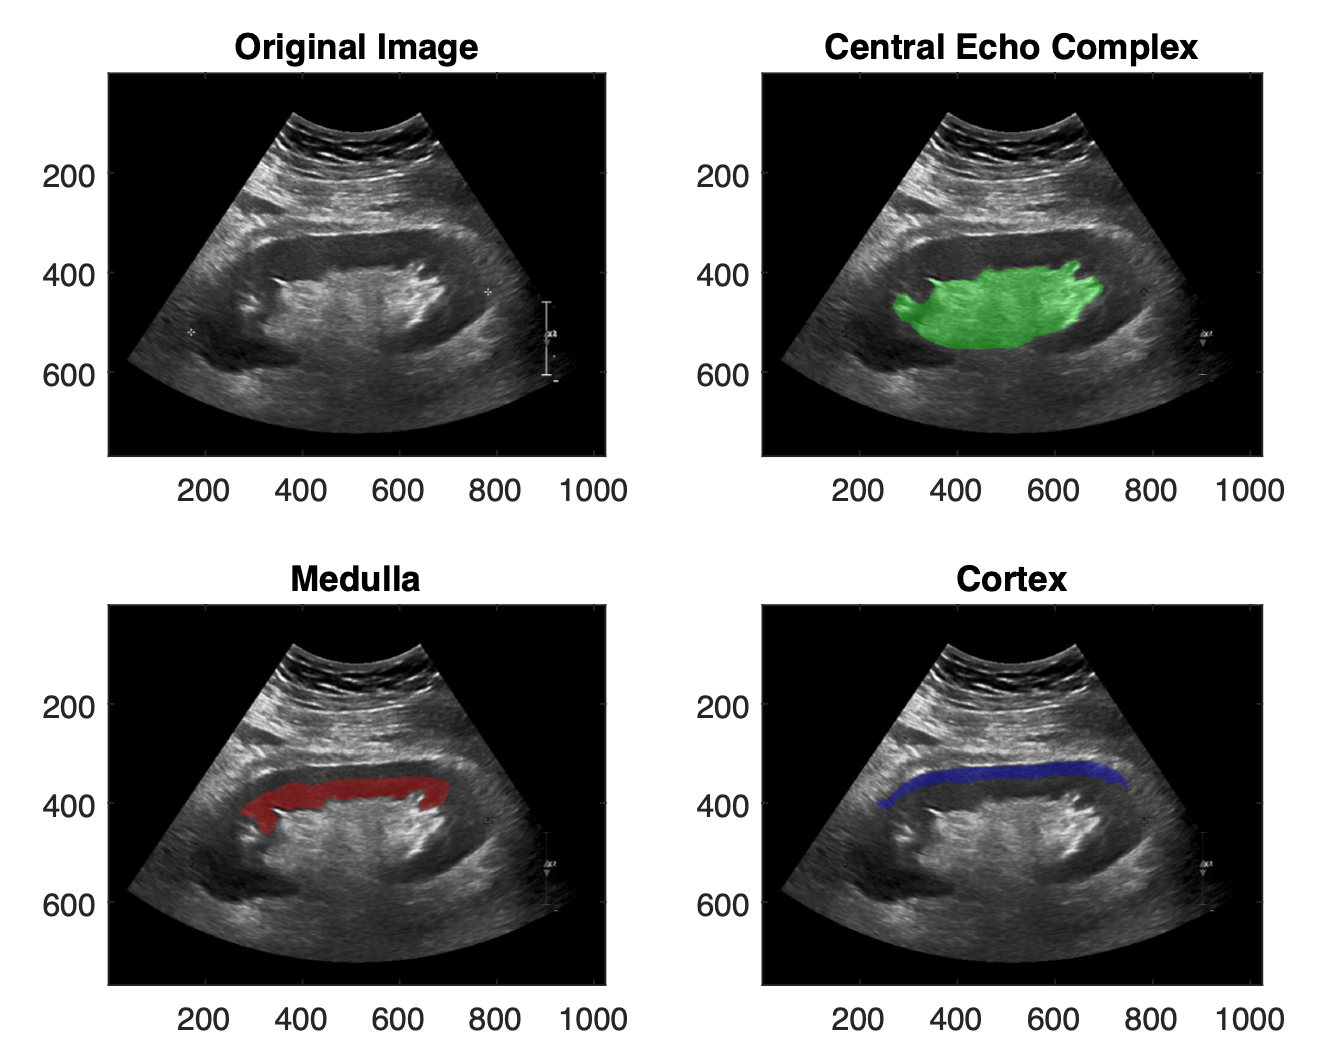

- Figure 2:

-

The three regions of the kidney that are extracted by the nnU-net segmentation. (Top left) the anonymonized kidney ultrasound image, (top right) the central echogenic complex which constitutes several anatomical structures but visually in ultrasound appears amalgamated, (bottom right) the cortex, a thin layer on the outermost portion of the kidney, and (bottom left) the medulla, the innermost portion of the renal parenchyma.